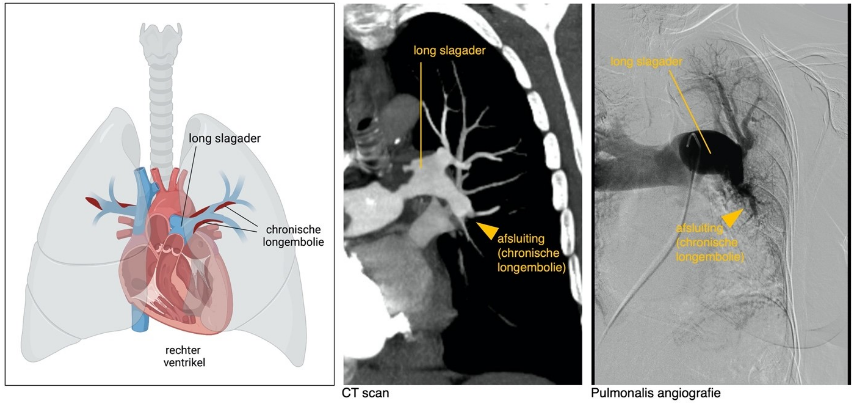

Bij Chronische Thrombo-Embolische Pulmonale Hypertensie (ook wel afgekort als CTEPH) ontstaat pulmonale hypertensie omdat de bloedvaten in de longen geheel of gedeeltelijk zijn afgesloten door bloedstolsels. Net als bij andere vormen van pulmonale hypertensie raakt de rechter harthelft overbelast. Bij een deel van de patiënten wordt CTEPH voorafgegaan door een episode van acute longembolieen. Normaal worden de stolsels na een episode van acute longembolieën door het lichaam zelf opgeruimd – bij CTEPH lijkt het mechanisme van opruimen verstoord. Echter, niet alle patiënten met CTEPH hebben een episode van acute longembolie doorgemaakt. Recent onderzoek suggereert dat stolsels ook ter plaatse in het longvaatbed kunnen ontstaan. Bij CTEPH zorgen de bloedstolsels voor een hoge weerstand: omdat het bloed niet goed door de longen kan stromen, stijgt de druk in de longbloedvaatjes. Als dit niet behandeld wordt, neemt de druk langzaam toe.

De onderzoeken die gedaan worden om CTEPH vast te stellen, komen grotendeels overeen met de onderzoeken die bij andere vormen van pulmonale hypertensie worden gedaan. Om de drukken te meten wordt rechtscatheterisatie gedaan, de conditie wordt in kaart gebracht met een fietstest (ergometrie) of een 6-minuten looptest. Bij CTEPH worden extra onderzoeken gedaan om de stolsels goed in kaart te brengen. Dit kan bijvoorbeeld door toediening van contrast tijdens de rechtscatherisatie. Dit wordt ook wel een pulmonalis angiografie genoemd, en geeft een afbeelding van de longbloedvaten en van verstoppingen. De verstoppingen kunnen ook in beeld worden gebracht door middel van een CT scan, waarbij contrast wordt toegediend. Deze onderzoeken zijn nodig om vast te stellen hoe de CTEPH het best behandeld kan worden.